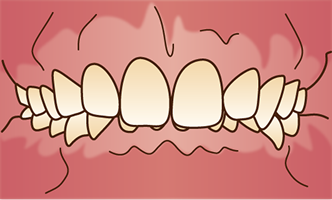

叢生

1. 叢生

歯がでこぼこに並んでいる状態のことを指します。

このような歯並びでは、歯磨きの際にブラシがしっかり届きにくく、歯垢が残りやすくなってしまいます。その結果、虫歯や歯槽膿漏の原因となることがあります。